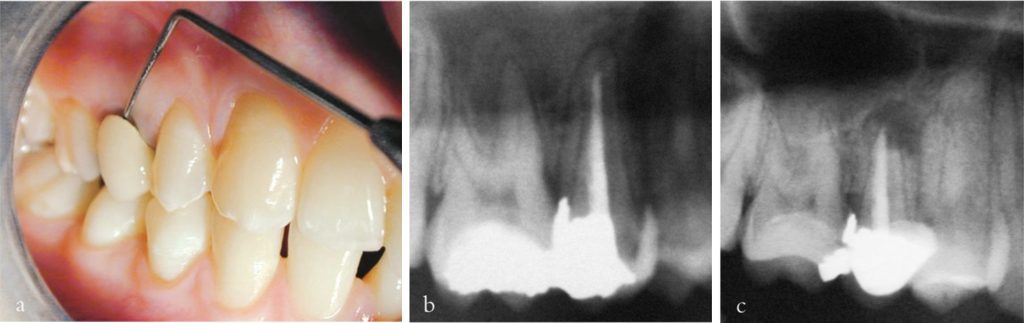

Trước hết cần đánh giá khả năng phục hồi răng, xét đến số lượng, chất lượng và vị trí mô thân răng còn lại, cũng như tình trạng nha chu.

Thăm dò cẩn thận quanh viền nướu bằng cây thăm dò nha chu giúp phát hiện các đặc điểm quan trọng như gãy dọc răng, có thể ảnh hưởng nghiêm trọng đến khả năng phục hồi và kế hoạch điều trị.

Nếu có bất kỳ nghi ngờ nào về khả năng phục hồi răng (xem chương 8) thì cần tháo bỏ hoàn toàn phục hồi hiện có để xác định rõ mức độ và vị trí mô răng lành còn lại.

Việc loại bỏ hoàn toàn phục hồi hiện tại được khuyến cáo trong nhiều trường hợp, vì có thể làm lộ ra các đường nứt ẩn không được phát hiện qua khám lâm sàng bên ngoài hay thăm dò nha chu.

Khi điều trị nội nha đã hoàn tất, răng cần được phục hồi càng sớm càng tốt nhằm đảm bảo vùng phục hồi kín khít, ngăn ngừa sự xâm nhập của dịch và vi khuẩn, bảo vệ răng khỏi gãy vỡ.

Các phục hồi kém chất lượng hoặc trì hoãn phục hồi có thể làm ảnh hưởng đến kết quả của điều trị nội nha, hoặc dẫn đến mất răng do các nguyên nhân không liên quan đến nội nha.

Nếu có đủ thời gian và khi có chỉ định, có thể đặt chốt sợi và trám kín buồng tủy ngay lập tức bằng vật liệu phục hồi. Đây là thời điểm lý tưởng để phục hồi, vì khoang mở tủy còn dễ tiếp cận và đã được khử khuẩn kỹ lưỡng, đồng thời răng vẫn đang được cô lập bằng đê cao su, tạo điều kiện tối ưu cho phục hồi.

Tuy nhiên, trong những trường hợp cần phục hồi phức tạp hơn, chẳng hạn như khi có kế hoạch phục hình phủ múi cho răng sau, răng có thể được phục hồi bằng một cùi giả dán — phần này sau đó có thể được sửa soạn cho phục hình phủ múi ở lần hẹn sau.